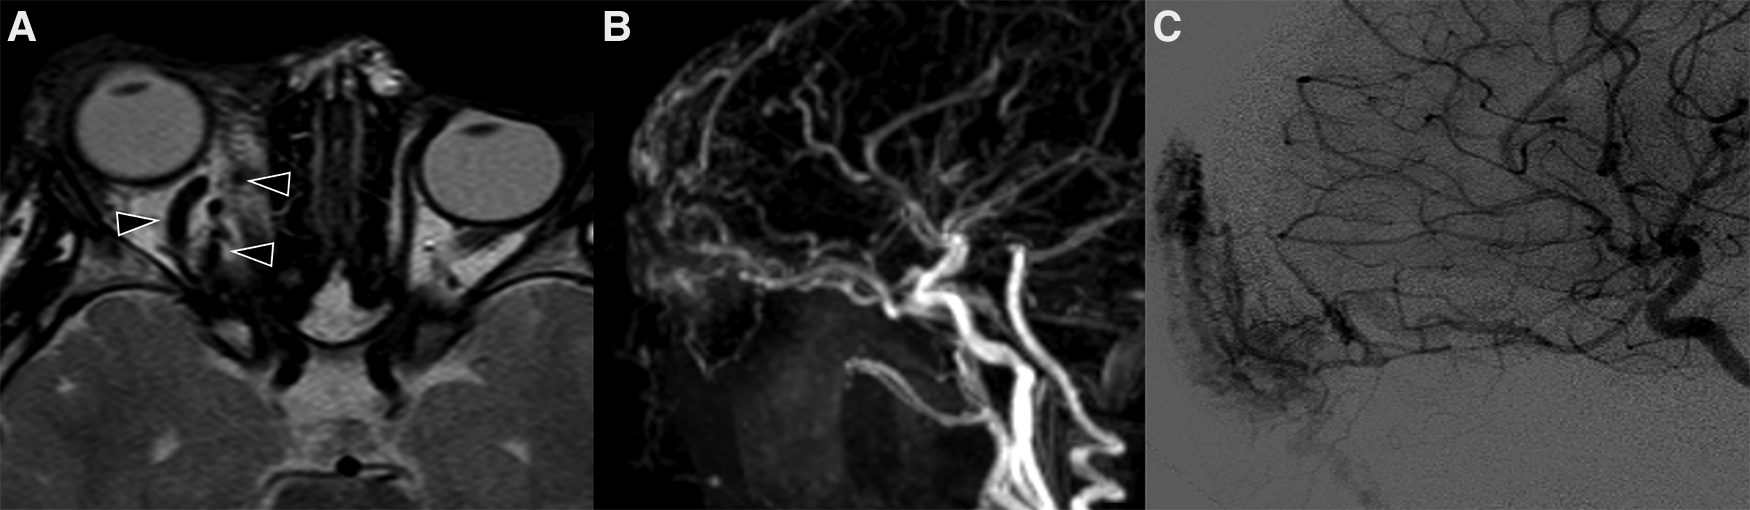

Noninvasive imaging is mandatory: it allows proper confirmation of diagnosis, sets a baseline for the patient and helps define the architecture of the malformation (68). The AVM has no parenchymal component and therefore it appears on gray-scale US as a poorly defined heterogeneous structure, usually surrounded by fat. At the color Doppler examination, the malformation is a high flow lesion: there are numerous vessels (“high vascular density”) with increased diastolic flow and arterialization of the draining vein. The spectral Doppler analysis shows arterial vessels with high-velocity flow and low resistive index (64). MRI and CT angiography are ideal noninvasive modalities for visualizing the entire course and extent of an AVM, to assess organ involvement and for planning endovascular or surgical management (13). MRI is the finest technique to estimate the expansion of the malformation and its rapports with adjacent structures (69). Dilated and tortuous vascular structures representing the hypertrophied feeding arteries and the draining veins are seen, appearing as prominent flow voids on spin-echo sequences, in the absence of a discrete enhancing soft tissue mass, thus aiding in the differential diagnosis with hemangiomas (Figure 11). In the very early cases, subtly hypertrophied vessels can be the only findings visible (Figure 11). In case of hemorrhage or thrombosis, foci of hypersignal on T1w images will be found (Figure 12). When small, the AVM usually involves a single compartment whereas in larger lesions or those that have been previously treated the nidus may be difficult to define as pronounced secondarily induced angiogenesis is present (56) or may be centered in more than one compartment. At MRA there is rapid enhancement of the tangle of vessels, with early enhancement of the draining veins (Figure 12). Intraosseous infiltration causes low marrow signal intensity on T1-weighted images (70). The introduction of time-resolved MRI sequences allowed to evaluate the hemodynamics of an AVM, giving the precise topography, mapped in time, of arterial feeders and venous drainage prior to DSA: the progressive opacification of the nidus and of the draining veins can be well-demonstrated and critical findings such as arterial or intranidal aneurysms or venous varices can be easily visualized (Figures 11, 12). In children, the identification or documentation of an AVM in the cerebro-facial region should prompt investigation for other clinically silent AVMs along the same metameric level due to possible syndromic associations (71). In case of suspected bone involvement or when the AVM is centered within the bone, CT and CTA may be the best imaging tools. Intraosseous AVMs present as osteolytic lesions with intense enhancement, as the lytic bony defects represent dilated intraosseous venous pouches or dilated draining veins (56). CT may also show complications such as bone thickening (or mature periosteal reaction), seen as a result of chronic venous hypertension, or osteolysis. DSA remains the most invaluable tool to confirm the diagnosis: it delineates the angioarchitecture and real-time hemodynamics of the AVMs with no venous contamination of the arterial phase, allowing also their endovascular treatment when necessary (Figures 11, 12).

Figure 11. Mr and DSA of a 2-year-old boy referred for follow-up of an orbital “hemangioma” treated with propranolol and worsening of proptosis. Axial T2 TSE sequence (A) shows markedly dilated and tortuous vessels (arrowheads) in the extra- and intra-conal compartments of the right orbit without a discrete parenchymatous component, raising the suspicion of an AVM. MR angiography revealed a tangle of vessels with a small nidus and early venous drainage (B). The findings were subsequently confirmed at DSA (C).